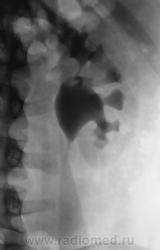

Гидронефротическая трансформация левой почки, стриктурное сужение пиелоуретрального сегмента, возможно наличие не рентген-контрастного камня.

Мы сами ломали себе голову. Оказывается, когда пациенту было 6 лет, ему была произведена операции, так как у ребенка развился гидронефроз в результате наличия аномальной артерии (со слов пациента). Документации, увы, нет.

Обычно детские урологи хорошо срабатывают на аномальный ход сосуда, но при длительном воздействие последствие остаются ввиде не полного стриктурного сужения.

По всей видимости, стриктура и в данном случае есть.